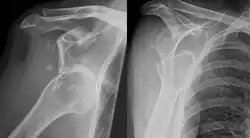

Eine Hill-Sachs-Läsion (auch Hill-Sachs-Delle genannt) ist eine Impression im Oberarmkopf durch die Schultergelenkspfanne, die den Knorpel oder aber Knochen und Knorpel betreffen kann. Es handelt sich bei dieser Verletzung um eine Folge von meist häufig wiederholter Schulterluxationen (Schulterausrenkungen). Je nach Richtung der Luxation findet sich ein hinterer, also dorsaler (vordere Luxation) oder vorderer – ventraler – (hintere Luxation) Hill-Sachs-Defekt. Das Eponym ehrt Harold Arthur Hill und Maurice David Sachs.

Der Defekt entsteht durch Druck des Pfannenrandes auf den Oberarmkopf im Zuge einer Schulterluxation. Der Defekt liegt dorso-lateral am Humeruskopf bei einer vorderen Schulterluxation. Bei einer hinteren Schulterluxation liegt die Hill-Sachs-Läsion ventro-cranial. Man spricht dann von einer inversen Hill-Sachs-Läsion. Meist tritt gleichzeitig eine Bankart-Läsion auf, also eine Abscherung des – je nach Luxationsrichtung vorderen oder hinteren – Pfannenrandes (Limbus), die ebenfalls nur den knorpeligen Rand oder Knorpel und Knochen betreffen kann.